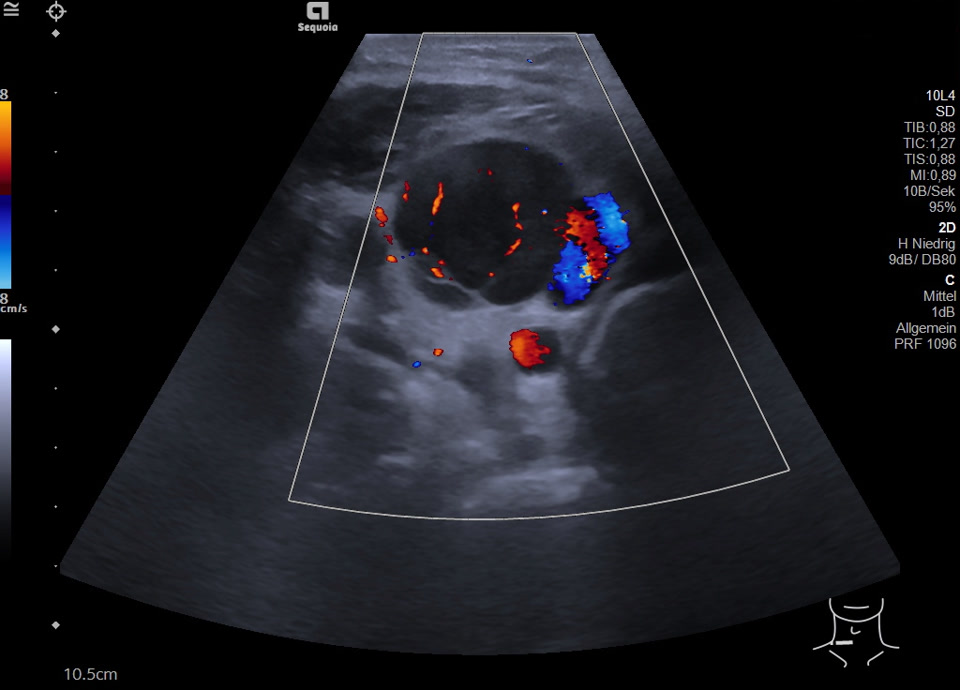

Venöse Kompression durch infiltrierte Lymphknoten (Bilder-/Videoserie)

Maligner Lymphknoten inguinal rechts bei Non-Hodgkin Lymphom